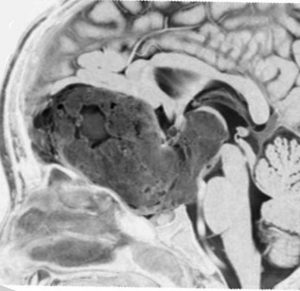

化学療法が有効なのは,上の画像のようにガドリニウム増強で強く増強されるタイプです,またT2強調画像で強い高信号になるものほど化学療法が有効です,要するに毛様粘液性星細胞腫の要素に化学療法が有効であるということです

この毛様細胞性星細胞腫はガドリニウムでほとんど増強されません(右側のMRI)から,化学療法を行っても小さくなりませんので,手術摘出する必要があります,実際に視床下部から発生したもの視交叉が犯されておらず,手術亜全摘出できました